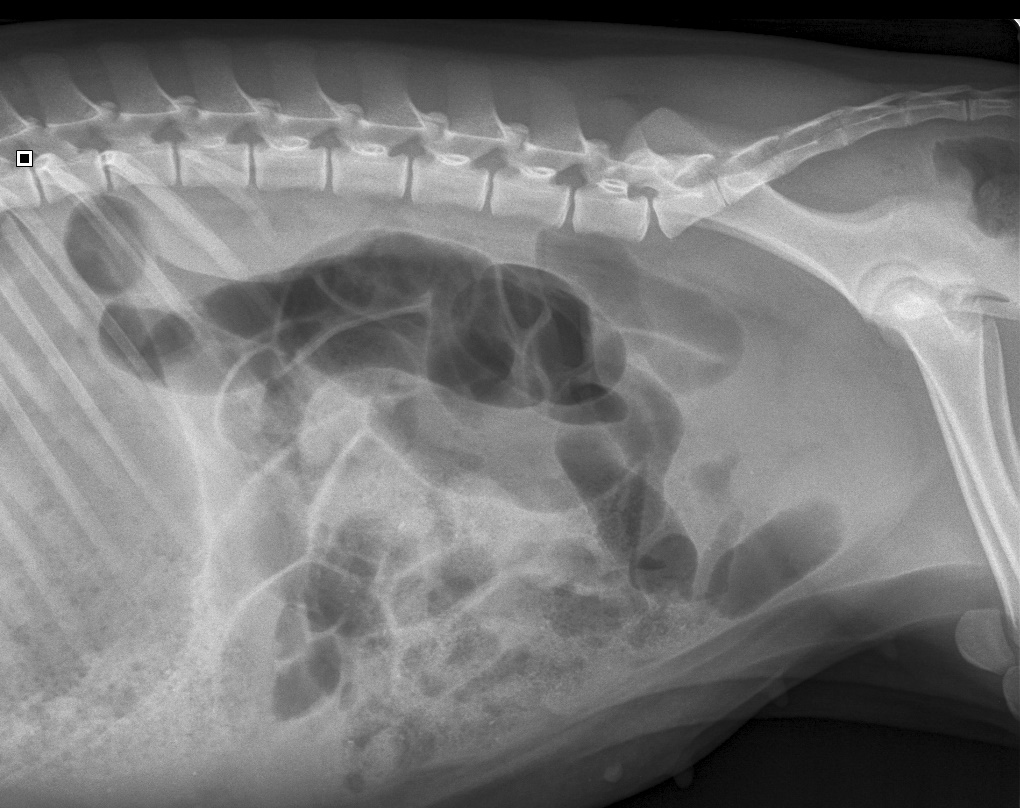

De röntgenfoto van de buik van Puk.

Goed te zien is dat er veel lucht (zwart) in de opgeblazen darm zit. Au!